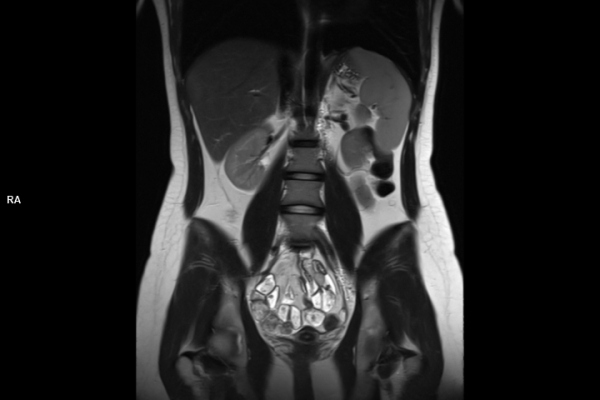

Detailbild MRT

Wir bieten ein breites Spektrum an Untersuchungen an, von Standarduntersuchungen der Gelenke, Organe oder großflächigen Körperregionen bis zu Spezialuntersuchungen zum Beispiel des Herzen oder der Gefäße. Zusätzlich werden Angiographien (Darstellung von Blutgefäßen), Endometriose-Abklärungen und Mamma-Untersuchungen durchgeführt. Genauere Details können Sie der MRT/CT-Übersicht und der Preisliste entnehmen, oder Sie wenden sich direkt an unser Team, das Sie gerne zur passenden Untersuchung berät.

Die MRT (Magnetresonanztomographie) arbeitet mit Magnetfeldern und Radiowellen und eignet sich besonders für Untersuchungen der Weichteile wie Gehirn, Muskeln oder Gelenke. Die CT (Computertomographie) nutzt Röntgenstrahlen und liefert schnelle, hochauflösende Bilder, insbesondere für Knochen, Lunge oder innere Organe. Die Wahl der jeweiligen Untersuchung richtet sich an das individuelle Krankheitsbild und wird bei der Überweisung festgelegt.